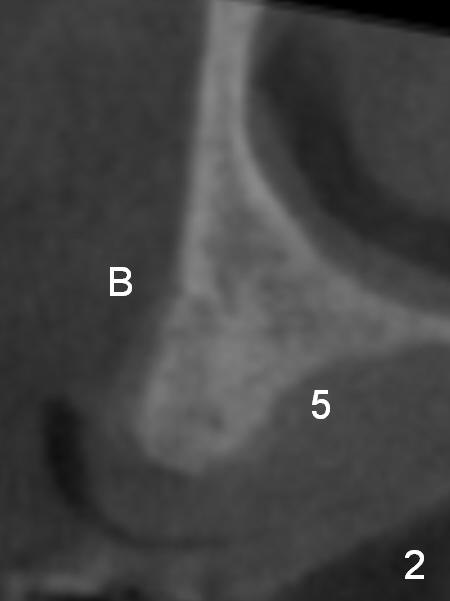

A 69-year-old man would consider implant option for his upper front teeth (Fig.1: #5-9) if there is no separate bone graft procedure. He does not want implants for his lower left molars (#18,19), since he has had a partial denture. In fact the bone at #5-9 is so thin that 2-3 mm 1-piece implants can be placed at #5,7 and 9 (Fig.2-5 (CT coronal sections (B: buccal)) for a 5-unit bridge (Fig.1). To support and increase the longevity of the latter, implants at #18,19 are mandatory (Fig.6,7).